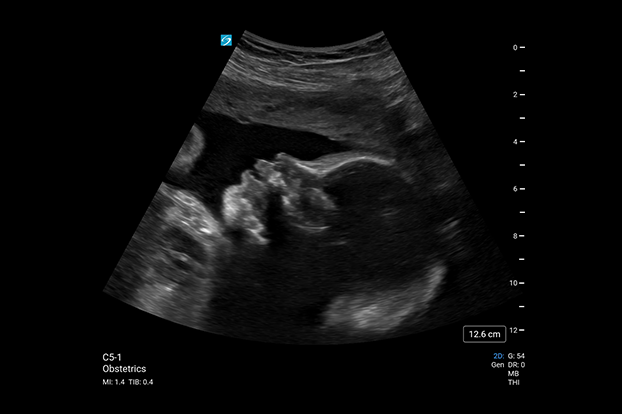

Sonosite PX, hastaları tedavi ederken ve teşhis ederken güven için en gelişmiş görüntü netliğimizi bünyesinde barındırır. Arayüz, geliştirilmiş verimlilik için dokunmatik ve fiziksel kontrolleri bir araya getirirken, uyarlanabilir yataydan dikeye çalışma yüzeyi optimum yatak başı ergonomisi sağlar. Sonografik dönüm noktalarını daha doğru bir şekilde görselleştirmek için Sonosite’in en gelişmiş görüntü netliği ve optimum hasta bakımı için ses kontrolü.

Üstün Görüntü Kalitesi

Daha iyi görüş, daha derin anlayış. Sonosite, klinisyenlerin en zorlu ihtiyaçlarını karşılamak için yeni bir görüntü performansı standardını yeniden tanımlıyor.